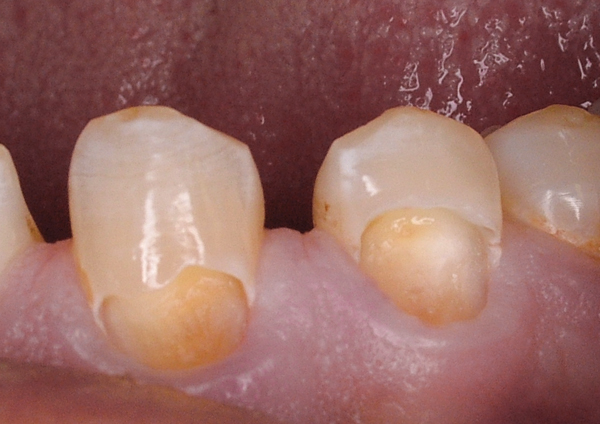

Fig 5. Class V preparations and non-carious cervical lesions can be restored with either a self-etch or etch-and-rinse adhesive.

Figure 5